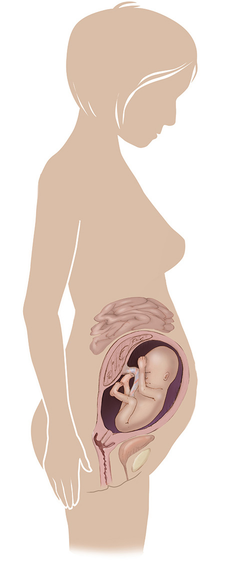

مراحل تطور الجنين أثناء الحمل

تطور الجنين خلال فترة الحمل على ثلاثة مراحل: أول 14 أسبوع من الحمل ، ثم تطوره بداية من الأسبوع 14 وحتى 28 أسبوعا ، ثم الثلث الأخير من 28 إلى 40 أسبوع من الحمل ... المزيد

مراحل تطور الحمل أسبوعيا بالصور

مراحل تطور الحمل أسبوعيا لكل من الأم والجنين داخل الرحم مدعومة بالصور التوضيحية ... المزيد